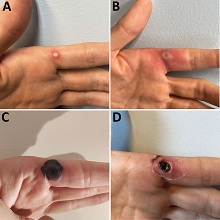

| Хемороиди или фиброваскуларни јастучићи аналног канала су део нормалне анатомске структуре и сматра се да су веома битни за одржавање континенције. Постоје два типа хемороида у односу на локализацију: спољашњи (у доњем делу аналног канала, испод зупчасте линије) и унутрашњи (у горњем делу аналног канала, изнад зупчасте линије). |

| Инфекција коже, захвата површни слој коже. У око 90% случајева обољења изазивач инфекције је СТАФИЛОКОК. Локални налаз се исполљава у виду црвенила након чега долази до стварања пустула и була које се пуне гнојним садржајем. |